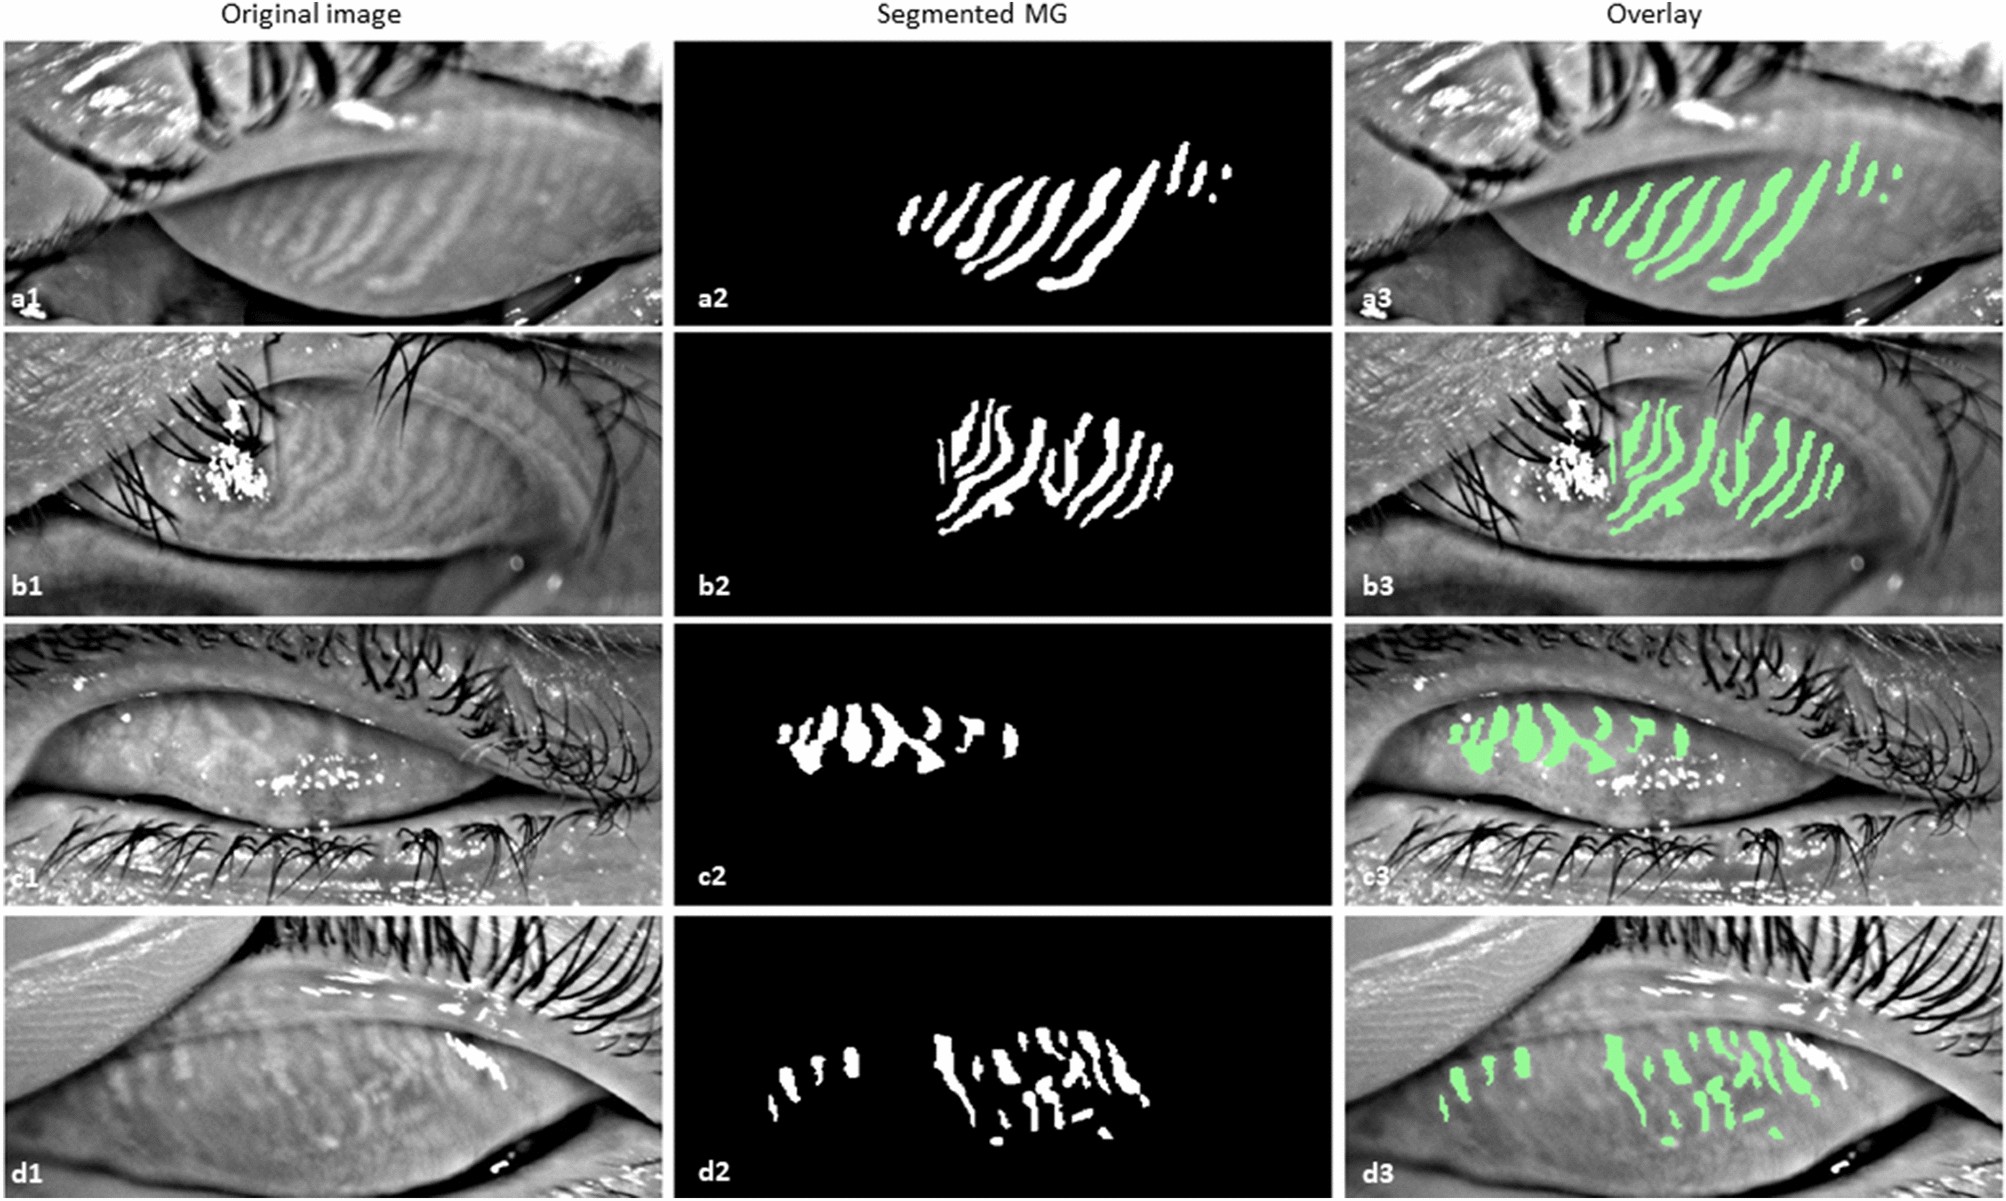

Figure 8

Example of MG segmentation on inferior quality images. (a1–a3) Out of focus image, segmented MGs, and overlay, (b1–b3) Eyelashes in the glands area image, segmented MGs, and overlay, (c1–c3) Partially everted upper eyelid image, segmented MGs, and overlay, and (d1–d3) Artifact of everting finger in the top left of the image, segmented MGs, and overlay.